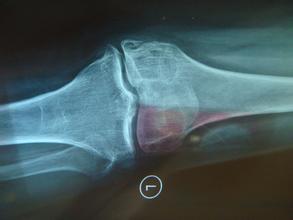

导读: 膝关节退行性关节炎又称膝关节肥大性关节炎,多见于老年人,因而也称作老年性关节炎。

导读: 继发性骨关节炎系指已知有骨关节疾病,由于原有疾病不能控制或未发现而产生了骨关节炎,是属于病理性的。继发性骨关节炎可发生在年轻人、中年人以及老年人身上。

导读: 骨关节炎可分为原发性以及继发性,原发性骨关节炎的病因目前尚未明确,一般认为与年龄、遗传、机械与外伤等因素有关。 骨关节炎可分为原发性以及继发性,原发性骨关节炎的病因目前尚未明确,一般认为与年龄、遗传、

导读: 关节肿胀是骨性关节炎常见、典型的症状表现,很多患者较初表现为滑膜炎,滑膜原本是比纸还要薄的一层膜,在关节腔内起着润滑的作用,同时人体的营养物质也是通过滑膜输送给骨头的,当滑膜出现炎症时,就会表现为肿胀

导读: 膝关节部位活动量比较大,几乎承受了身体大部分的重量,因此负荷是比较大,如果不注意保护,很容易引起膝关节疾病。有些人在活动的时候,会感觉到膝盖有摩擦音,那么这是怎么回事呢?云骨专家提醒大家,膝盖有摩擦音